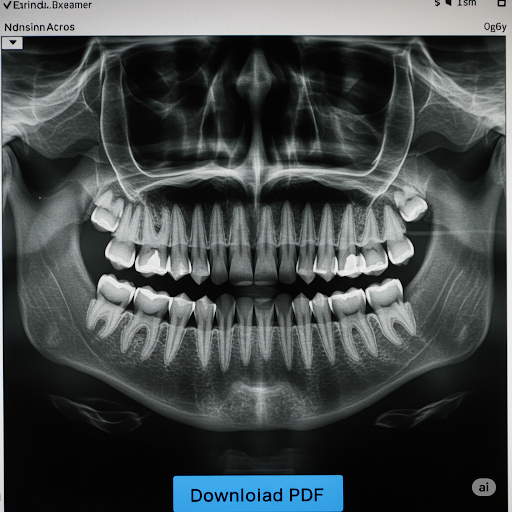

Dental X-rays (radiographs) utilize controlled bursts of X-ray radiation to generate images of oral structures. Denser tissues like teeth and bone absorb more radiation, appearing light on the X-ray film, while less dense soft tissues (gums, cheeks) allow more radiation to pass through, appearing darker. This enables dentists to visualize hidden structures, detect cavities, bone loss, infections, and abnormalities not visible during a standard examination. As a key diagnostic and preventive tool, dental X-rays offer distinct advantages that maintain their position as a preferred imaging modality within dentistry.